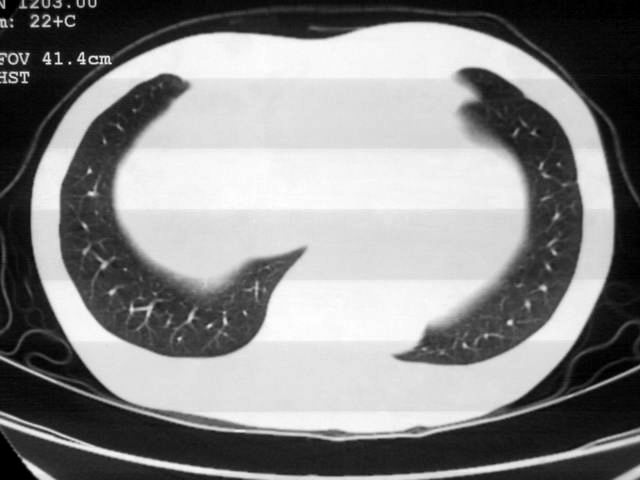

以下是引用苯小孩在2007-4-24 19:46:00的发言:[br]左下肺内侧基底段,见类圆形病灶,边缘清晰光滑.强化后轻中度强化.<平扫第4层面似有从腹主动脉相连血管影,可惜强化扫描这层没有抓住>考虑:左下肺隔离症.建议dsa或薄层强化重建观察.

以下是引用同在2007-4-24 20:11:00的发言:[br]考虑肺隔离症